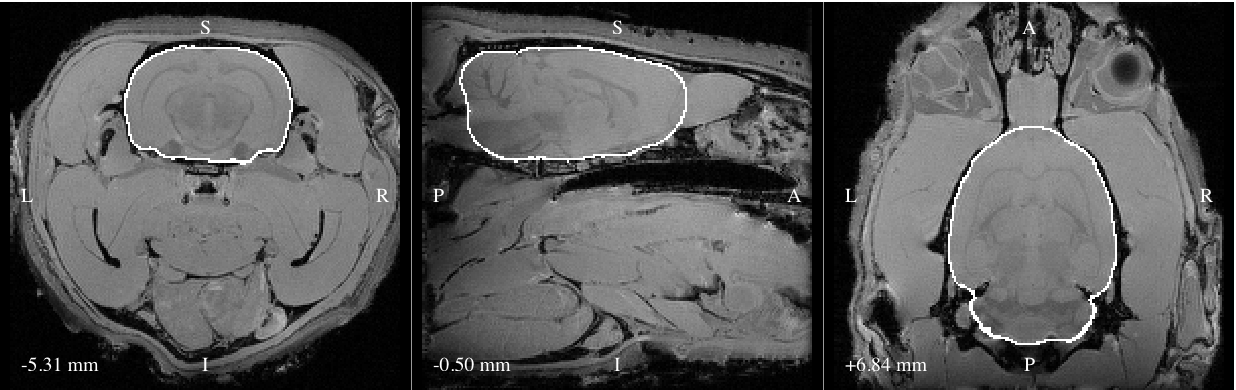

Description:Outline of brain mask generated from a T1-weighted image